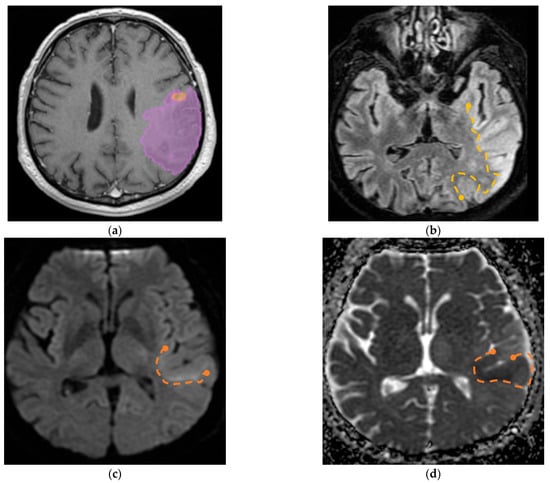

Furthermore, we identified a specific case involving a patient diagnosed with GBM with visible invasion in the adjacent parenchyma; the aspect on MRI imaging is seen in Figure 9.

(a) Mdbrain processing of MRI brain acquisition (DICOM) (Scale 1:20)—purple area corresponding to T2W FLAIR hyperintensity; (b) T2W FLAIR (Scale 1:16), axial plane, manual delimitated (yellow dotted line) hyperintense area corresponding to edema/parenchymal invasion; (c) DWI (Scale 1:25), axial plane, discreet hyperintensity in the immediate subcortical area, manually delineated (orange dotted line); (d) ADC map (Scale 1:26)—hypo-intensity corresponding to the DWI hypersignal, suggesting parenchymal invasion, manually delimitated (orange dotted line) (approval was obtained from the Ethics Committee of the University of Medicine and Pharmacy “Grigore T. Popa” Iasi).